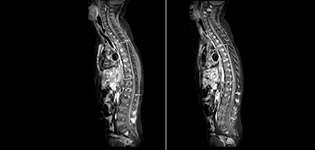

Routinemäßige homogene Fettsuppression unter praktisch allen Bedingungen mit mDIXON TSE

Philips mDIXON TSE ist ein Zweipunkt-DIXON-Verfahren, das Wasser- und Fettsignale trennt und so eine zeiteffiziente, fettfreie Bildgebung auch bei komplexen neurologischen Anatomien ermöglicht. „mDIXON TSE ist eine der signifikantesten Verbesserungen bei Bildgebungssequenzen, die wir am PCH bisher realisiert haben“, sagt Dr. Miller. „Dank der multiparametrischen Erfassung können wir Bilder mit Fettsuppression und entsprechende T2-Bilder ohne Fettsuppression in derselben Sequenz aufnehmen. Außerdem war es bei den bisherigen Methoden möglich, dass diese durch Artefakte aufgrund einer ungünstigen Patientenanatomie oder durch Bedienfehler beeinträchtigt wurden. Mit mDIXON verfügen wir jetzt jedoch über eine robuste und zuverlässige Methode zur Fettsuppression.“ Historisch gesehen bereitet die Fettsuppression am Ende des Sichtfeldes Schwierigkeiten, insbesondere bei der Bildgebung der gesamten Wirbelsäule und bei diffizilen Patientenanatomien wie dem unteren Halsbereich. „Aufgrund der einzigartigen Fettsuppressionseigenschaften von mDIXON treffen diese Probleme jedoch nicht mehr zu“, erläutert Dr. Miller. „Wir erhalten routinemäßig eine homogene Fettsuppression unter praktisch allen Bedingungen. Darüber hinaus konnten wir auch die Effizienz steigern, weil wir keine Sequenzen mehr aufgrund solcher technischen Einschränkungen wiederholen müssen.“

mDIXON TSE macht den Unterschied

„mDIXON TSE hat unsere Diagnosesicherheit erhöht, weil Abweichungen, bei denen die Fettsuppression für die Diagnose entscheidend ist, definitiv abgeklärt werden können, zum Beispiel metastatische Erkrankungen oder ossale Veränderungen.“

„mDIXON TSE erweist sich bei Patienten mit Läsionen oder pathologischen Befunden im Weichteilgewebe wie Gesicht und Hals am nützlichsten sowie bei Patienten mit kontrastverstärkenden Abweichungen, die mit Fettsuppression am besten sichtbar sind“, so Dr. Miller weiter. „Unsere gesamte Wirbelsäulenbildgebung enthält mittlerweile mDIXON T2-Bilder auf reiner Wasserbasis, und dies ermöglicht uns die Erkennung von Pathologien, die bei einer Bildgebung ohne Fettsuppression zum Beispiel von Knochenverletzungen nicht sichtbar wären. Außerdem ist es nicht nötig, weitere TSE-T2-Standardbilder aufzunehmen, weil die mDIXON In-Phase-Bilder gleichwertig mit TSE-T2-Standardbildern sind.“